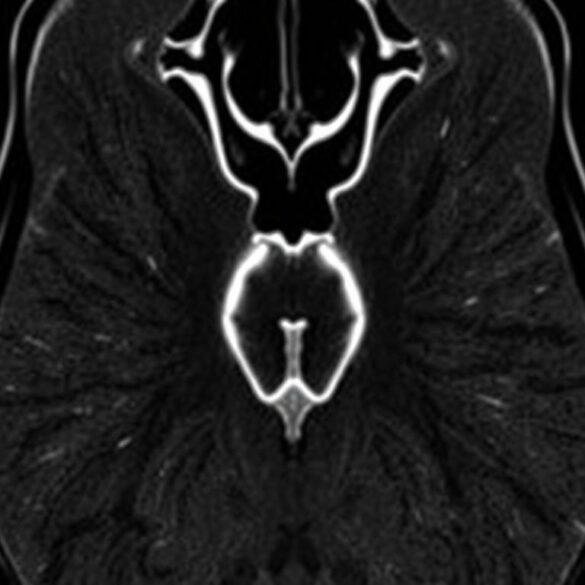

Компьютерная томография давно перестала быть чем-то пугающим и редким. Для многих жителей КТ в Южно-Сахалинске стала повседневным инструментом диагностики: быстрое...